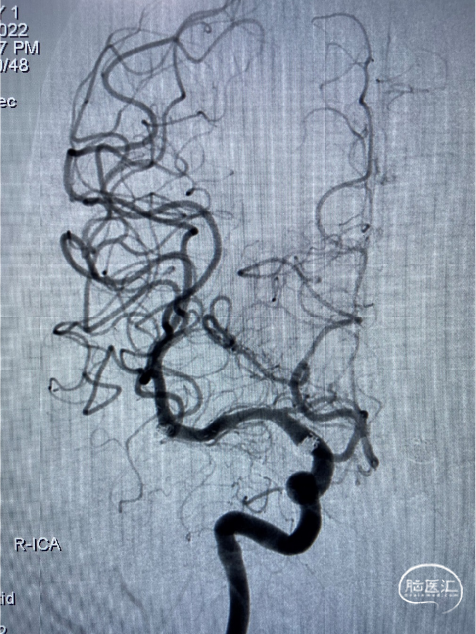

患者静吸复合全麻造影示:左侧颈内动脉交通段可见约5.5mm×3.0mm大小动脉瘤,瘤颈宽2.7mm,右侧大脑中动脉可见2.0mm×2.1mm大小动脉瘤,瘤颈宽1.8mm。右侧颈内动脉交通段可见约6.3mm×5.8mm大小动脉瘤,瘤颈宽4.2mm,左侧大脑前动脉A3段可见约1.8mm×1.8mm大小动脉瘤,瘤颈宽1.3mm。右侧胚胎型大脑后动脉。

术中三维所见

6F导引导管至于左侧C2段,在Synchro-0.014 200cm微导丝携带下将PROWLER SELECT PLUS微导管送至左侧大脑中动脉M2段,在ASAHI CHIKAI-0.014 200mm微导丝携带下将Echelon 10微导管送至瘤腔内。

路图引导下将4mm×12cm 3D弹簧圈(EV3)沿微导管置入动脉瘤腔内暂不解脱,沿支架微导管将4.5mmx22mm支架(Enterprise)置入左侧颈内动脉交通段。继续填入弹簧圈